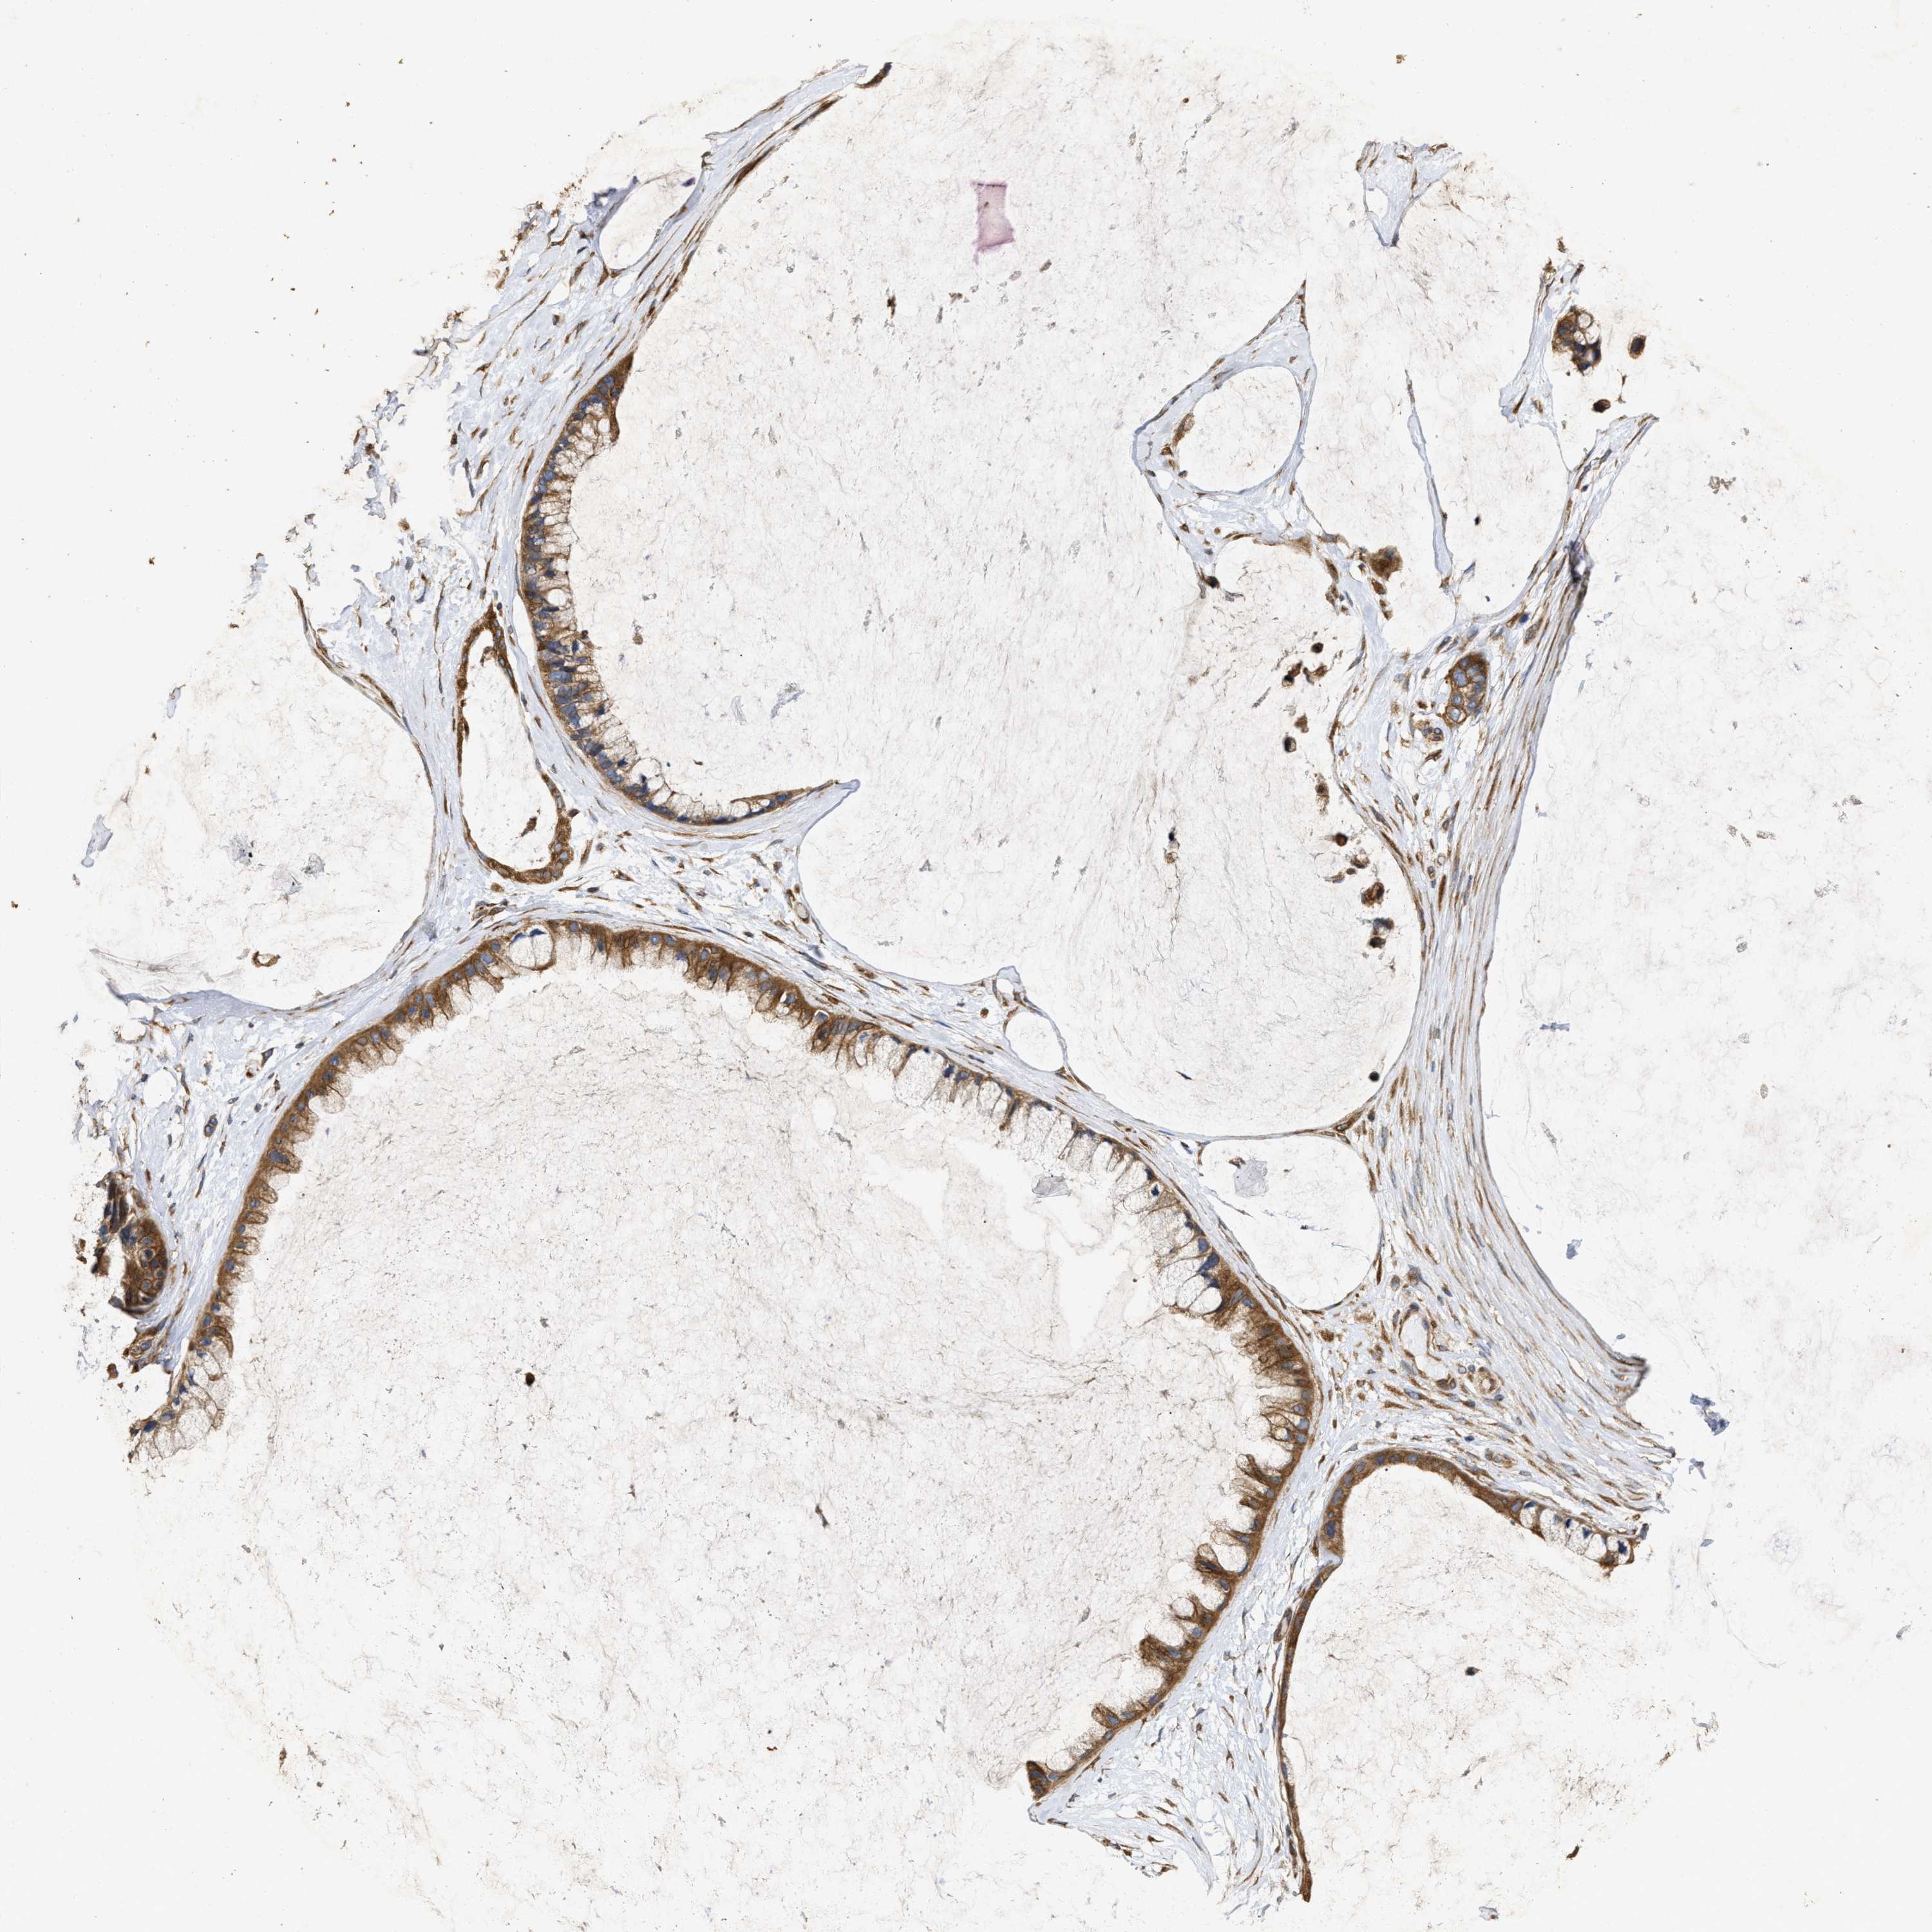

OVARIAN CANCER - Protein expressioni

A mouse-over function shows sample information and annotation data. Click on an image to view it in a full screen mode. Samples can be filtered based on level of antibody staining by selecting one or several of the following categories: high, medium, low and not detected. The assay and annotation is described here.

Note that samples used for immunohistochemistry by the Human Protein Atlas do not correspond to samples in the TCGA dataset.

Antibody stainingi

Antibody staining in the annotated cell types in the current human tissue is reported as not detected, low, medium, or high, based on conventional immunohistochemistry profiling in selected tissues. This score is based on the combination of the staining intensity and fraction of stained cells.

Each image is clickable and will lead to virtual microscopy that enables deeper exploration of all samples and also displays staining intensity scores, fraction scores and subcellular localization as well as patient and tissue information for each sample.

Antibody HPA018127

Antibody HPA027887

Antibody CAB012302

Staining

High

Medium

Low

Not detected

Intensity

Strong

Moderate

Weak

Negative

Quantity

>75%

75%-25%

<25%

None

Location

Nuclear

Cytoplasmic/membranous

Cytoplasmic/membranous,nuclear

Cystadenocarcinoma, serous, NOS

Carcinoma, endometroid

Cystadenocarcinoma, mucinous, NOS

Carcinoma, NOS